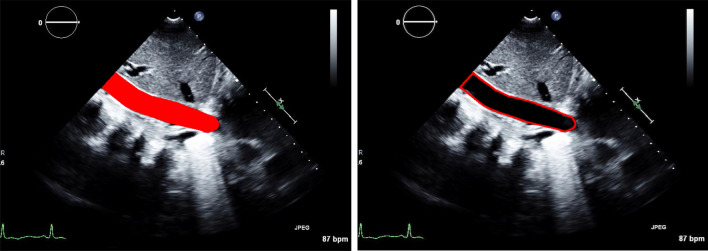

Current noninvasive estimation of right atrial pressure (RAP) by inferior vena cava (IVC) measurement during echocardiography may have significant inter-rater variability due to different levels of observers' experience. Therefore, there is a need to develop new approaches to decrease the variability of IVC analysis and RAP estimation. This study aims to develop a fully automated artificial intelligence (AI)-based system for automated IVC analysis and RAP estimation. We presented a multi-stage AI system to identify the IVC view, select good quality images, delineate the IVC region and quantify its thickness, enabling temporal tracking of its diameter and collapsibility changes. The automated system was trained and tested on expert manual IVC and RAP reference measurements obtained from 255 patients during routine clinical workflow. The performance was evaluated using Pearson correlation and Bland-Altman analysis for IVC values, as well as macro accuracy and chi-square test for RAP values. Our results show an excellent agreement (r=0.96) between automatically computed versus manually measured IVC values, and Bland-Altman analysis showed a small bias of [Formula: see text]0.33 mm. Further, there is an excellent agreement ([Formula: see text]) between automatically estimated versus manually derived RAP values with a macro accuracy of 0.85. The proposed AI-based system accurately quantified IVC diameter, collapsibility index, both are used for RAP estimation. This automated system could serve as a paradigm to perform IVC analysis in routine echocardiography and support various cardiac diagnostic applications.

目前超声心动图中通过下腔静脉(IVC)测量无创右房压(RAP)的方法,由于观察者经验水平的不同,可能存在显著的评分差异。因此,有必要开发新的方法来降低IVC分析和RAP估计的变异性。本研究旨在开发一个基于人工智能(AI)的全自动IVC分析和RAP估计系统。我们提出了一种多阶段人工智能系统来识别IVC视图,选择高质量的图像,描绘IVC区域并量化其厚度,从而实现对其直径和可折叠性变化的时间跟踪。在常规临床工作流程中,对该自动化系统进行了专家手动IVC和RAP参考测量的训练和测试。IVC值采用Pearson相关分析和Bland-Altman分析,RAP值采用宏观精度和卡方检验。我们的结果显示,自动计算的IVC值与人工测量的IVC值之间的一致性很好(r=0.96), Bland-Altman分析显示了0.33 mm的小偏差。此外,自动估计的RAP值与手动导出的RAP值之间存在非常好的一致性([公式:见文本]),宏观精度为0.85。本文提出的基于人工智能的系统准确量化了IVC直径和可折叠性指数,两者都用于RAP估计。该自动化系统可作为常规超声心动图中进行IVC分析的范例,并支持各种心脏诊断应用。